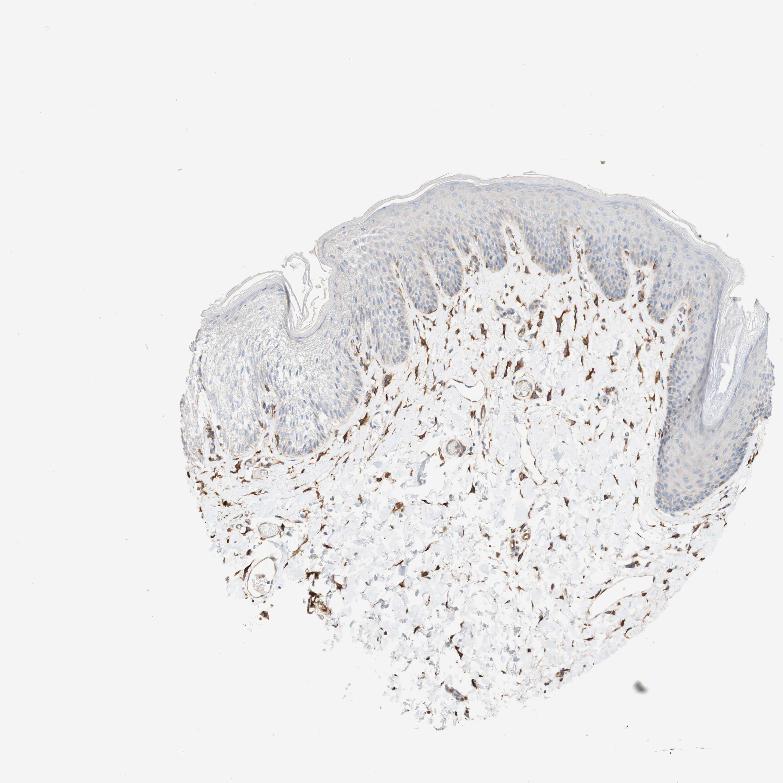

SKIN 2 - Antibody stainingi

Antibody staining in the annotated cell types in the current human tissue is reported as not detected, low, medium, or high, based on conventional immunohistochemistry profiling in selected tissues. This score is based on the combination of the staining intensity and fraction of stained cells.

Each image is clickable and will lead to virtual microscopy that enables deeper exploration of all samples and also displays staining intensity scores, fraction scores and subcellular localization as well as patient and tissue information for each sample.

Antibody HPA011811

Epidermal cells Low